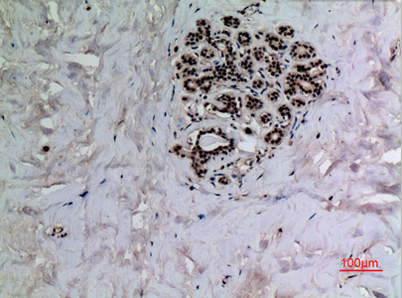

Product name: p53 (Acetyl Lys372) rabbit pAb

Dilutions: Western Blot: 1/500 - 1/2000. IHC-p: 1:100-300 ELISA: 1/20000. Not yet tested in other applications.

Immunogen: The antiserum was produced against synthesized Acetyl-peptide derived from human p53 around the Acetylation site of Lys372. AA range:331-380